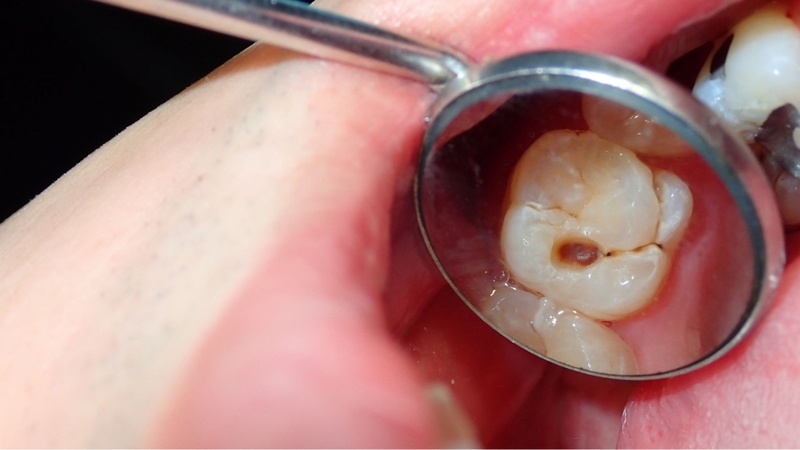

Răng vĩnh viễn mới mọc đóng vai trò quan trọng trong chức năng ăn nhai và định hình hàm răng lâu dài. Tuy nhiên, khi răng vĩnh viễn mới mọc bị sâu vào tủy, nhiều người không khỏi lo lắng liệu tình trạng này có nguy hiểm và ảnh hưởng gì đến sức khỏe răng miệng hay không.

Sâu răng ở răng vĩnh viễn mới mọc là vấn đề không hiếm gặp, đặc biệt ở trẻ em và thanh thiếu niên. Nếu tổn thương tiến triển sâu vào tủy răng, nguy cơ biến chứng sẽ tăng cao, đòi hỏi phải được phát hiện và can thiệp kịp thời để bảo tồn răng.

Răng vĩnh viễn mới mọc bị sâu vào tủy là tình trạng khiến nhiều phụ huynh và bệnh nhân lo lắng, đặc biệt khi xảy ra ở trẻ em và thanh thiếu niên. Đây là giai đoạn răng chưa phát triển hoàn thiện, vì vậy nếu tổn thương tủy xảy ra, nguy cơ biến chứng sẽ cao hơn so với răng đã trưởng thành.

Sâu răng tiến triển nặng

Những lỗ sâu lớn sát tủy hoặc đã xâm nhập vào buồng tủy tạo điều kiện cho vi khuẩn xâm nhập hệ thống ống tủy. Nếu không được điều trị kịp thời, tình trạng này có thể tiến triển thành: